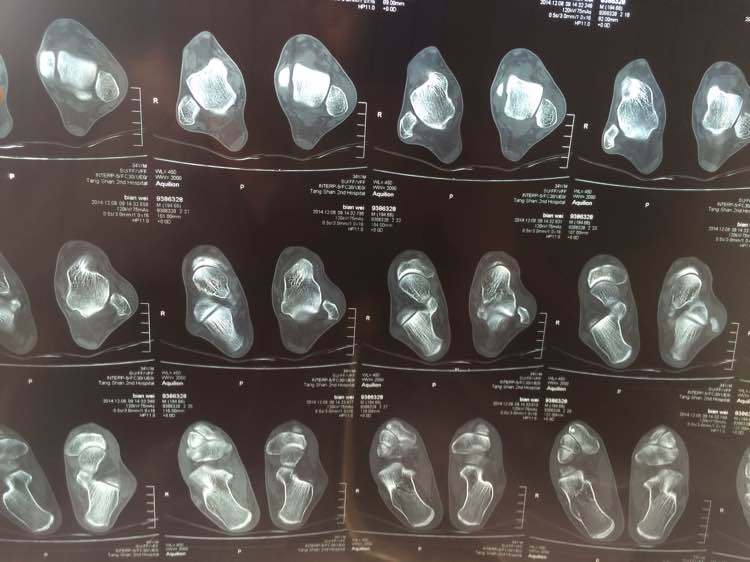

求高手刚我看看 骨折了吗

医院说骨折了 找的老中医说错位了 我晕了

左胫骨下段外侧端撕脱性骨折。